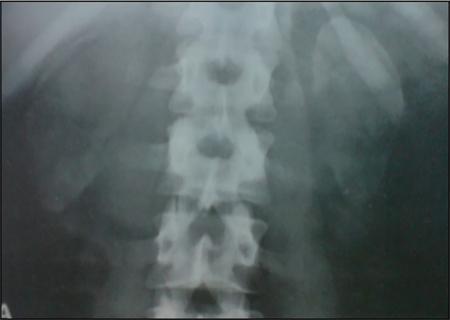

Skeletal abnormalities like spina bifida, lumbar vertebral anomalies, osteoporotic changes, looser zones and bone tumours can also be seen on the plain radiograph. The association of skeletal anomalies such as spina bifida, caudal regression, and wide pubic symphysis may help in further defining associated syndromic criteria.

Features suggestive of secondary hyperparathyroidism like medullary nephrocalcinosis, rugger jersey spine, subchondral bone resorption around the sacroiliac joints, subtendinous bone resorption at ischial tuberosity and dystrophic soft tissue calcification can also be seen.